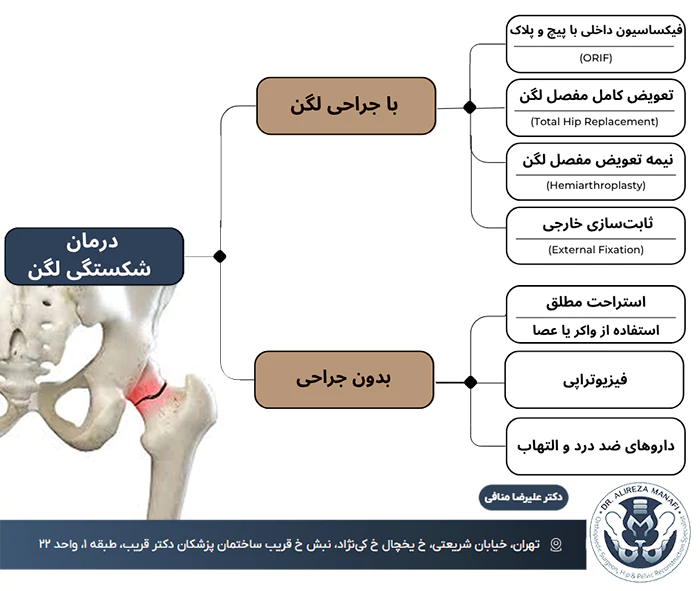

درمان شکستگی لگن اهمیت خیلی زیادی دارد بهویژه در سالمندان؛ چرا که این نوع شکستگی میتواند بهسرعت منجر به عوارض شدید، بیتحرکی طولانیمدت و حتی مرگ شود. انتخاب روش مناسب درمان، به عواملی مثل شدت آسیب، سن، وضعیت عمومی و محل دقیق شکستگی بستگی دارد.

شاید بپرسید که کدام روشهای درمانی موثرتر هستند؟ چگونه میتوان بهترین زمان برای جراحی را تعیین کرد؟ و چه اقداماتی روند بهبود را تسریع میکند؟ در ادامه همراه ما باشید تا بهترین متدهای درمانی این شکستگی را بررسی کنیم.

درمان شکستگی لگن بدون جراحی

در برخی موارد، بهویژه زمانی که شکستگی جزئی است و استخوانها جابجا نشدهاند، میتوان از روشهای غیرجراحی استفاده کرد. این روشها بیشتر برای بیمارانی به کار میرود که جراحی برای آنها خطرناک است یا شرایط جسمانی خاصی دارند.

روشهای درمان شکستگی لگن بدون جراحی معمولاً شامل موارد زیر است:

- استراحت مطلق در بستر برای کاهش فشار روی لگن

- داروهای ضد درد و ضد التهاب برای کنترل درد و کاهش التهاب ناحیه

- استفاده از واکر یا عصا برای جلوگیری از وارد شدن وزن به پا

- فیزیوتراپی زودهنگام برای جلوگیری از تحلیل عضلات و آمادگی برای بازگشت تدریجی به فعالیتهای روزمره

درمان شکستگی لگن با جراحی

درمان شکستگی لگن با جراحی معمولاً در مواردی انجام میشود که شکستگی شدید بوده، استخوانها جابهجا شدهاند یا نمیتوانید بدون جراحی دوباره مثل قبل راه بروید. انتخاب نوع جراحی بستگی به سن بیمار، نوع شکستگی، وضعیت سلامت عمومی و میزان آسیب به مفصل دارد. در ادامه، مهمترین روشهای جراحی برای درمان شکستگی لگن را بررسی میکنیم:

فیکساسیون داخلی با پیچ و پلاک (ORIF)

در این روش، جراح با استفاده از پیچ، پین و صفحات فلزی، قطعات شکستهشده استخوان لگن را به هم متصل و در جای صحیح خود نگه میدارد. این کار باعث میشود استخوانها بهدرستی جوش بخورند و لگن دوباره ثبات خود را به دست آورد. معمولاً این روش در بیمارانی استفاده میشود که شکستگی همراه با جابهجایی استخوان دارند و مفصل هنوز سالم است.

تعویض کامل مفصل لگن (Total Hip Replacement)

در این روش، سر استخوان ران و حفره لگنی که آسیب دیدهاند بهطور کامل با پروتز جایگزین میشوند. این جراحی بیشتر برای افراد مسن، بهویژه آنهایی که پوکی استخوان دارند یا مفصلشان بهشدت آسیب دیده، توصیه میشود. تعویض مفصل لگن نهتنها شکستگی را درمان میکند بلکه درد و محدودیت حرکتی را هم کاهش میدهد.

نیمه تعویض مفصل لگن (Hemiarthroplasty)

در این روش فقط سر استخوان ران با یک قطعه فلزی جایگزین میشود، در حالی که بخش دیگر مفصل (حفره لگن) دستنخورده باقی میماند. این روش مخصوصا برای سالمندانی که شکستگی فقط در قسمت فوقانی استخوان ران رخ داده و بافت مفصل لگنی هنوز سالم است، انحجام میشود.

ثابتسازی خارجی (External Fixation)

در موارد خاص که به دلیل شرایط عمومی نمیتوانید جراحی داخلی انجام دهید، یا زمانی که شکستگی همراه با آسیبهای دیگر مانند خونریزی شدید باشد، از تثبیتکنندههای خارجی استفاده میشود. این ابزارها خارج از بدن قرار گرفته و با پیچهایی به استخوان متصل میشوند تا وضعیت لگن را پایدار کنند تا زمانی که برای جراحی آماده شوید یا استخوان خودبهخود ترمیم شود.